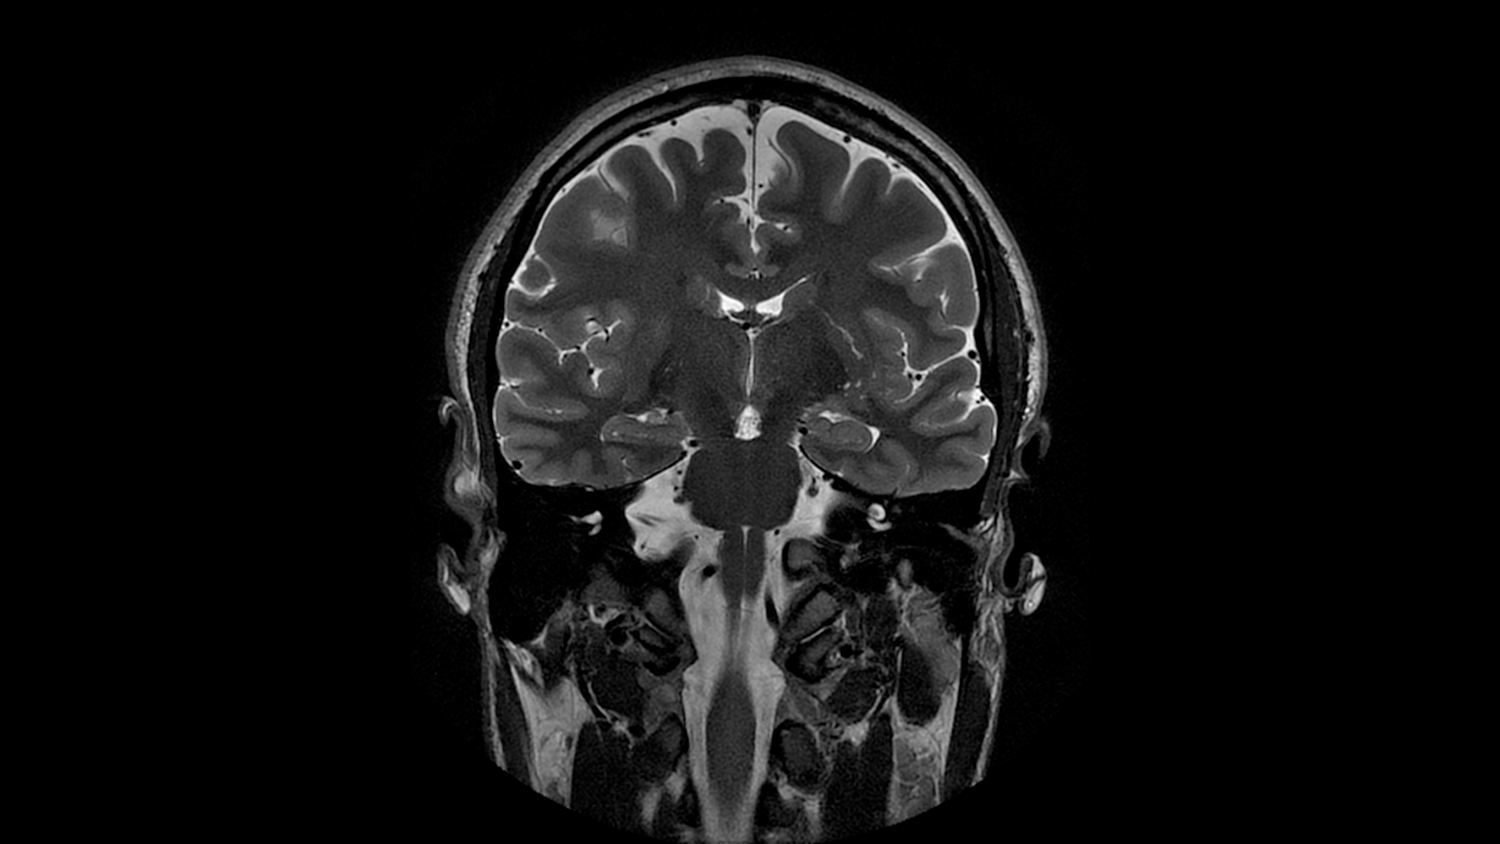

Анатомия мозга: Рентгеновские снимки для презентаций